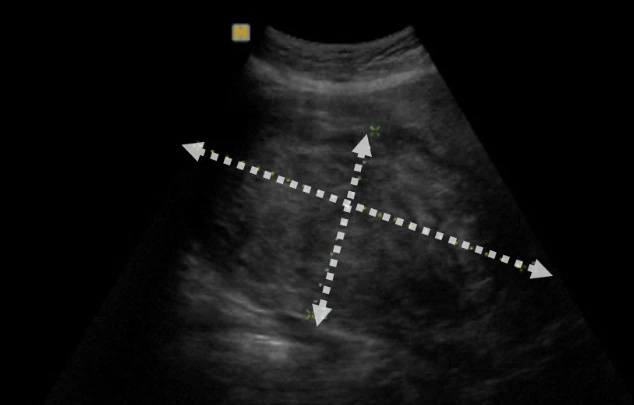

복부 초음파로 살펴본 자궁근종, 14cm 크기의 자궁근종이었으며 질 초음파로는 평가하는데 어려움이 있었다.

CT나 MRI와 같은 영상검사와 다르게 초음파는 병원을 옮길 때마다 다시 확인하는 경우가 많습니다. 검사가 간단하고 비용이 CT나 MRI에 비해 저렴하다는 것도 하나의 이유이겠지만, 초음파는 검사자 간의 차이가 많이 발생하고, 타 병원에서 가져온 영상 자료를 이용하면 자궁근종의 위치와 모습을 파악하기 어렵기 때문입니다.